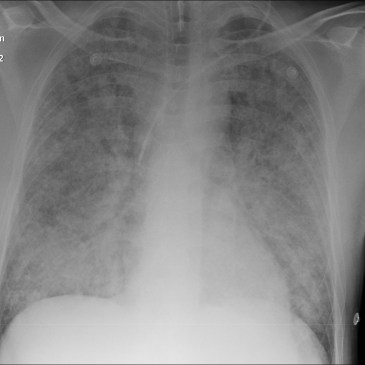

Vodcast A Case to Consider A 42 year old male presents to the Emergency Department with Progressive SOB and Myalgias. He has a fever and tachycardia at triage. His initial BP is 90/60. He is treated with broad spectrum antibiotics and 3.5L of crystalloid IV Fluid On day 2 of admission Chest X-ray shows progressive … More Acute Respiratory Distress Syndrome (ARDS)